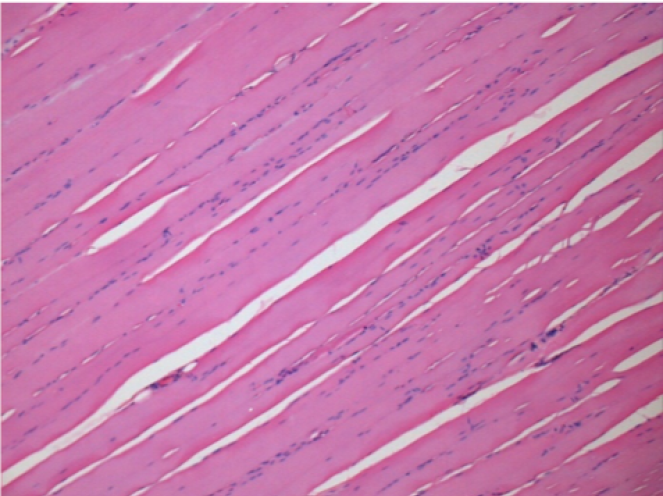

Л: Претибіальний м'яз - без лікування

Через 10 днів після ін'єкції Ендопіл 0,1 мл в правий претибіальний м'яз.

Тут можна побачити утворення вакуолей, які оточені лімфоцитами. Вакуолі відрізняються від некрозу тканини. Присутність лімфоцитів пов'язана з проникністю клітинних мембран.